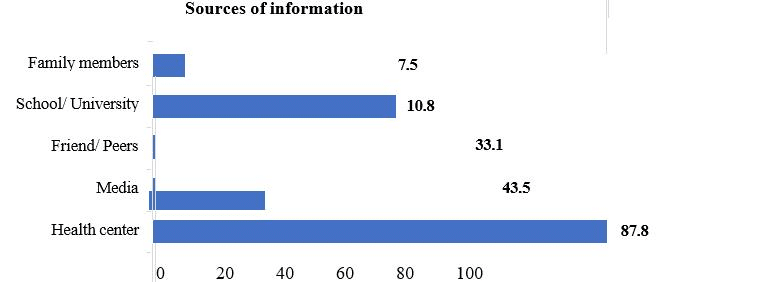

Knowledge, Attitude, and Practice Towards Hepatitis B Vaccine Among Clinical Year Students in University of Gondar College of Medicine and Health Sciences, Northwest, Ethiopia: An Institution-based Cross-sectional Study

Background: Hepatitis B is a viral infection that attacks the liver and can cause both acute and chronic disease. It...Read More